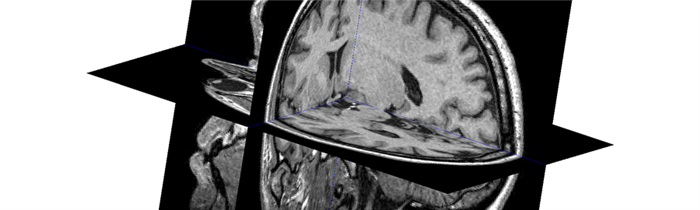

— Насколько эффективно МРТ при диагностике опухоли головного мозга?

Данный метод позволяет определить наличие опухоли на самых ранних стадиях. Если обнаружены признаки развития раковых клеток в головном мозге, пациенту вводят контрастный препарат для изучения распространения и степени онкологического заболевания. В результате диагностики врачи получают снимки новообразований с достаточно полной информацией: расположение, размер и форма. МРТ эффективно даже в случае наличия очень мелких опухолей, новообразований, расположенных вблизи кости или в стволе головного мозга. МРТ — надежный и эффективный метод диагностики онкологических заболеваний головного мозга.